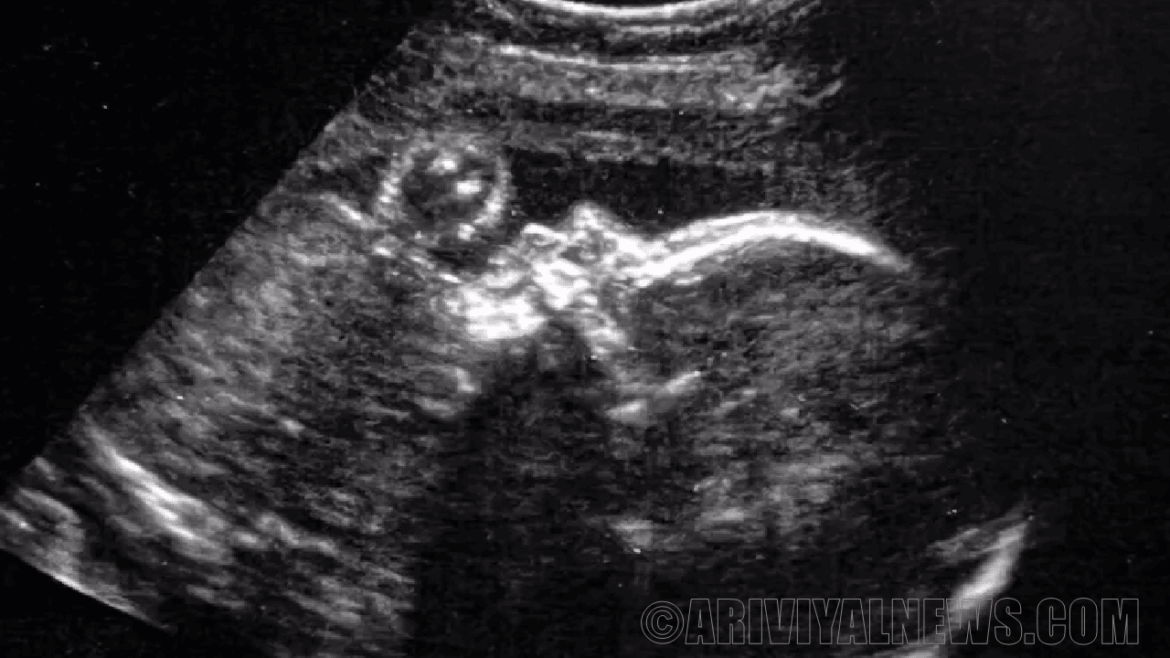

டென்வர் மற்றும் கென்யாட்டா கோல்மன் கர்ப்பமாகி 34 வாரங்கள் மற்றும் இரண்டு நாட்களில் “டிரான்ஸ்யூடெரின்” செயல்முறையை மேற்கொண்டனர். (சிஎன்என் படி, 30 வாரங்களில் அல்ட்ராசவுண்டிற்குப் பிறகு VOGM கண்டறியப்பட்டது.)